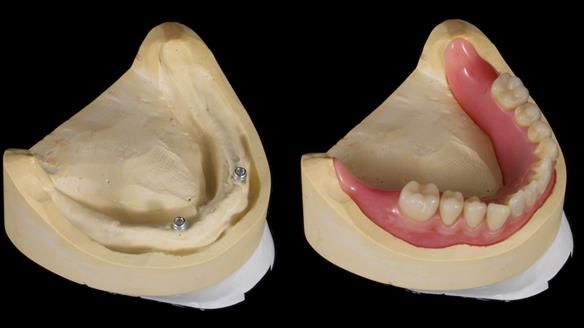

Welcome to my Newsletter 57, where I show the making and fitting of complete dentures supported by upper and lower dental implants for Alisdair. This issue provides a comprehensive overview of the entire protocol workflow.

1. The four implants appear clinically and radiographically healthy, though their longevity is uncertain.

2. The upper denture, horseshoe-shaped and metal-reinforced, rocks on the ridge, causing wear on Locator abutments and a fractured upper right tooth.

The detailed clinical situation and treatment process are outlined below, with clinical work provided by me and technical work by Rowan Garstang. New complete implant supported complete dentures were made. The new upper denture had ‘almost’ full palatal extension for the non-splinted implants following ITI guidelines. A decision was reached to retain the worn Kerator attachments, as their removal could potentially accelerate implant failure. The treatment spanned five visits for denture fitting and one review. Alisdair expressed great satisfaction with the treatment, noting a significant enhancement in his overall quality of life.